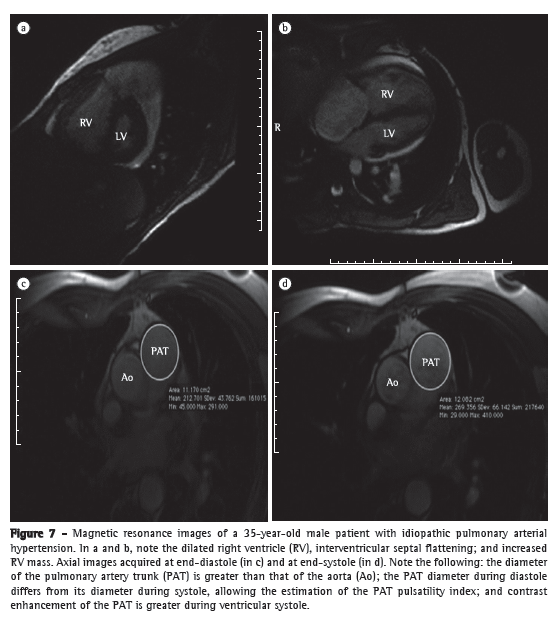

In patients with PH, cardiac MRI is especially important for the assessment of the following parameters (Figure 7):

Ventricular morphology-CT images that make it possible to determine the size and volume of the heart chambers, as well as wall thickness, and muscle mass. End-diastolic RV volume is significantly increased in PH. One group of authors(52) studied the role of cardiac MRI in the prognostic evaluation of patients with PH and observed that patients with increased diastolic RV volume and reduced systolic RV volume or reduced diastolic LV volume have a worse prognosis at 12-month follow-up. The study suggests that MIR can also be used as a tool for monitoring and evaluating treatment response.(52) In addition, MRI can analyze RV mass, which, during increased afterload, is significantly increased. Evidence suggests that RV mass index correlates well with mPAP.(53)

Ventricular function-dynamic images that reproduce the entire cardiac cycle can be obtained with electrocardiographic gating and have high accuracy and reproducibility in the analysis of ventricular function.(54) Another interesting tool is the evaluation of diastolic RV dysfunction and the behavior of the RV following treatment.

Interventricular septal configuration-distortions in the normal morphology of the interventricular septum can be observed in patients with PH. These quantifiable changes correlate with mPAP and prognosis.(55)

Flow analysis-volumetric flow measurements can be obtained with the use of contrast material and sequential image acquisition, which provides data for the determination of cardiac output, the evaluation of valvular regurgitation, the assessment of diastolic ventricular filling, and the quantification of cardiac shunts. Cardiac MRI has advantages over thermodilution in the acquisition of cardiac output measurements because it is noninvasive, it is less dependent on changes from one cardiac cycle to another, and it is not as strongly affected by TR.(56)

Myocardial viability assessment-the assessment of myocardial contrast after gadolinium infusion can directly show nonviable areas of the myocardium. One group of authors(57) described a pattern of myocardial contrast enhancement in patients with PH. Delayed contrast enhancement was present within the RV insertion points and interventricular septum of 23 of the 25 patients studied. The extent of delayed contrast enhancement correlated with worse RV function.